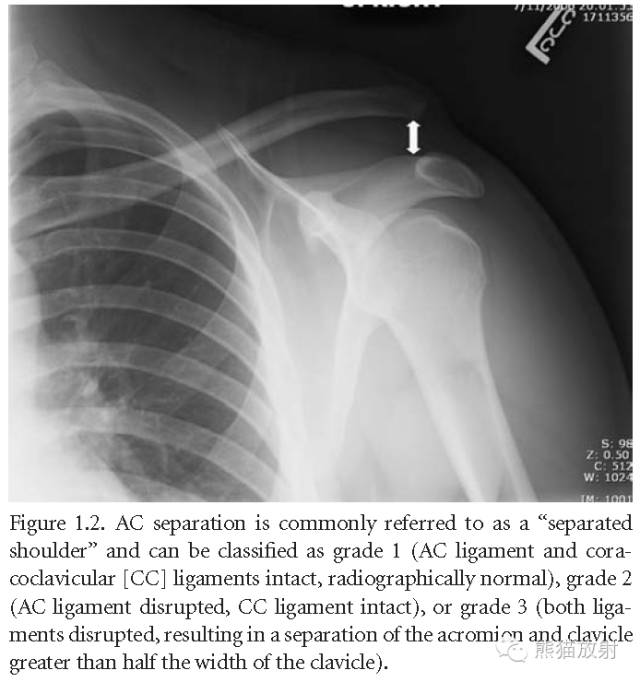

肩锁关节脱位:分为三级:1级(肩锁韧带和喙锁韧带完整,平片正常),2级(肩锁韧带撕裂,喙锁韧带正常),3级(两个韧带同时撕裂,肩峰与锁骨分离,距离超过锁骨宽度的一半)。